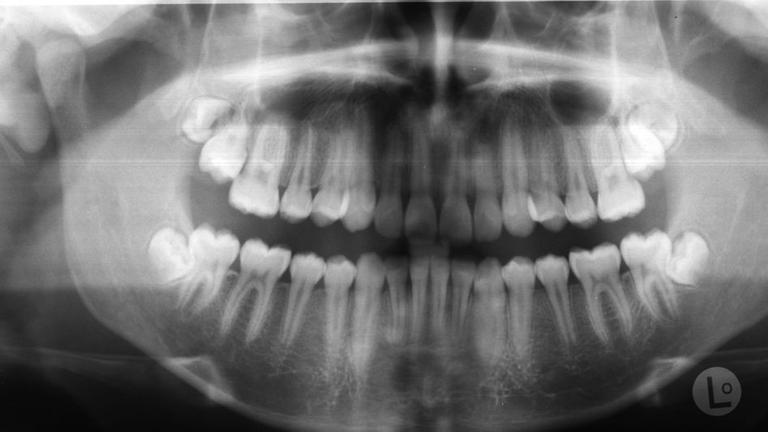

41+ schlau Bilder Wann Müssen Die Weisheitszähne Raus : Ziehen oder nicht? - ZDFmediathek - Die weisheitszähne (dens molaris tertius) zeigen sich in der regel erst nach dem 16.. Wann muss ein weisheitszahn raus? Lebensjahr sind die zahnwurzeln noch nicht vollständig entwickelt, der eingriff verläuft daher meist komplikationsloser. Die rede ist von unseren weisheitszähnen. Oft bleiben sie dann vollständig im kiefer eingeschlossen (retiniert) oder können nur teilweise durchkommen (teilretiniert). Hiermit würde ich sie gerne um eine zweitmeinung bitten, denn natürlich werde ich diese fragen auch meiner kieferorthopädin stellen.

Die rede ist von unseren weisheitszähnen. Dann sind die wurzeln ausgeformt, aber der umgebende knochen ist noch leicht zu entfernen, erklärt hüttmann. Auch wenn sie entzündet sind, müssen die weisheitszähne raus. Ob und wann ein weisheitszahn entnommen werden muss, hängt ganz individuell von der stellung im kiefer und seiner aktivität ab. Beim herauswachsen würden sie so gegen die zahnwurzel des benachbarten backenzahns („siebener) drücken.

Ob weisheitszähne ihre nachbarn verschieben, belegen studien nicht einheitlich. Wann die weisheitszähne entfernt werden müssen? Bei anhaltenden beschwerden besteht die gefahr, dass die wurzel des nachbarzahns unwiderruflich geschädigt wird. Normalerweise kommen die großen zähne im alter von ungefähr 17 bis 30 jahren.doch gibt es auch einige sonderheiten beim zeitpunkt, wann ein weisheitszahn entsteht. Da sie allerdings sehr weit hinten liegen und durch schlechte platzverhältnisse manchmal nicht gut genug gepflegt werden können, entsteht an diesen zähnen leichter karies. Das ist beispielsweise dann der fall, wenn die zähne schräg im kiefer liegen. Das verursacht nicht nur schmerzen, sondern kann den zahn irreparabel beschädigen. Zudem gibt sie tipps, was patienten nach einem eingriff beachten sollen. Wann müssen weisheitszähne gezogen werden? Auch mit einem schwachen immunsystem kann man problemlos ein zahn entfernen. Wenn weisheitszähne normal und problemlos durchbrechen, müssen sie in der regel nicht gezogen werden. Die rede ist von unseren weisheitszähnen. Müssen die weisheitszähne raus, dann sollte das jedenfalls möglichst bald geschehen.

Bei folgenden anhaltspunkten müssen weisheitszähne entfernt werden: Weisheitszähne müssen entfernt werden, wenn sie nur teilweise durchbrechen, kaputt sind, nicht genügend platz haben oder schief bzw. Das ist beispielsweise dann der fall, wenn die zähne schräg im kiefer liegen. Schließlich achtet der zahnarzt auf die entsprechende hygiene, wir sind nicht mehr im. Ihre entwicklung ist häufig erst im erwachsenenalter abgeschlossen.

Berlin: Ersatz aus der Ecke: Weisheitszähne müssen nicht ... from www.aachener-nachrichten.de Normalerweise kommen die großen zähne im alter von ungefähr 17 bis 30 jahren.doch gibt es auch einige sonderheiten beim zeitpunkt, wann ein weisheitszahn entsteht. Die weisheitszähne (dens molaris tertius) zeigen sich in der regel erst nach dem 16. Grundsätzlich müssen die weisheitszähne nicht entfernt werden. Ich(15,w) hab heute gemerkt,dass mein weisheitszahn rechts unten anfängt rauszukommen und ich glaube schief. Häufig verfügen weisheitszähne über zu wenig platz im gebiss, liegen schräg und können demzufolge nicht normal wachsen. Weisheitszähne müssen entfernt werden, wenn sie nur teilweise durchbrechen, kaputt sind, nicht genügend platz haben oder schief bzw. Die spritze ist harmlos, die merkst du kaum. Wann müssen weisheitszähne gezogen werden?